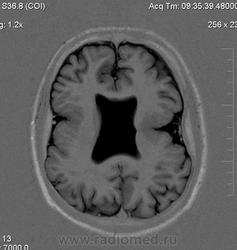

Мужчина 32 лет. Из анамнеза: перинатальное повреждение ЦНС, ДЦП, дизартрия, правосторонний верхний монопарез. С 16 лет приступы эпилепсии.

Аплазия прозрачной перегородки. Шизэнцефалия с открытыми краями в лобно-теменной области слева. Шизэнцефалия с закрытыми краями в лобной области справа? Утолщение коры по контуру расщелин и в области глазничной извилины правой лобной доли. Микрогирия? Гиперостоз костей свода черепа. Уважаемые коллеги, возможно я ошибаюсь, или есть еще аномалия?

На мой взгляд, полимикрогирия двусторонняя (конвекситальные отделы дорзальных отделов лобных долей и частично теменных, а также в базальном отделе полюса правой лобной доли) + закрытая шизенцефалия левой лобно-теменной области. Аплазия прозрачной перегородки (как признаки лобарной голопрозенцефалии).